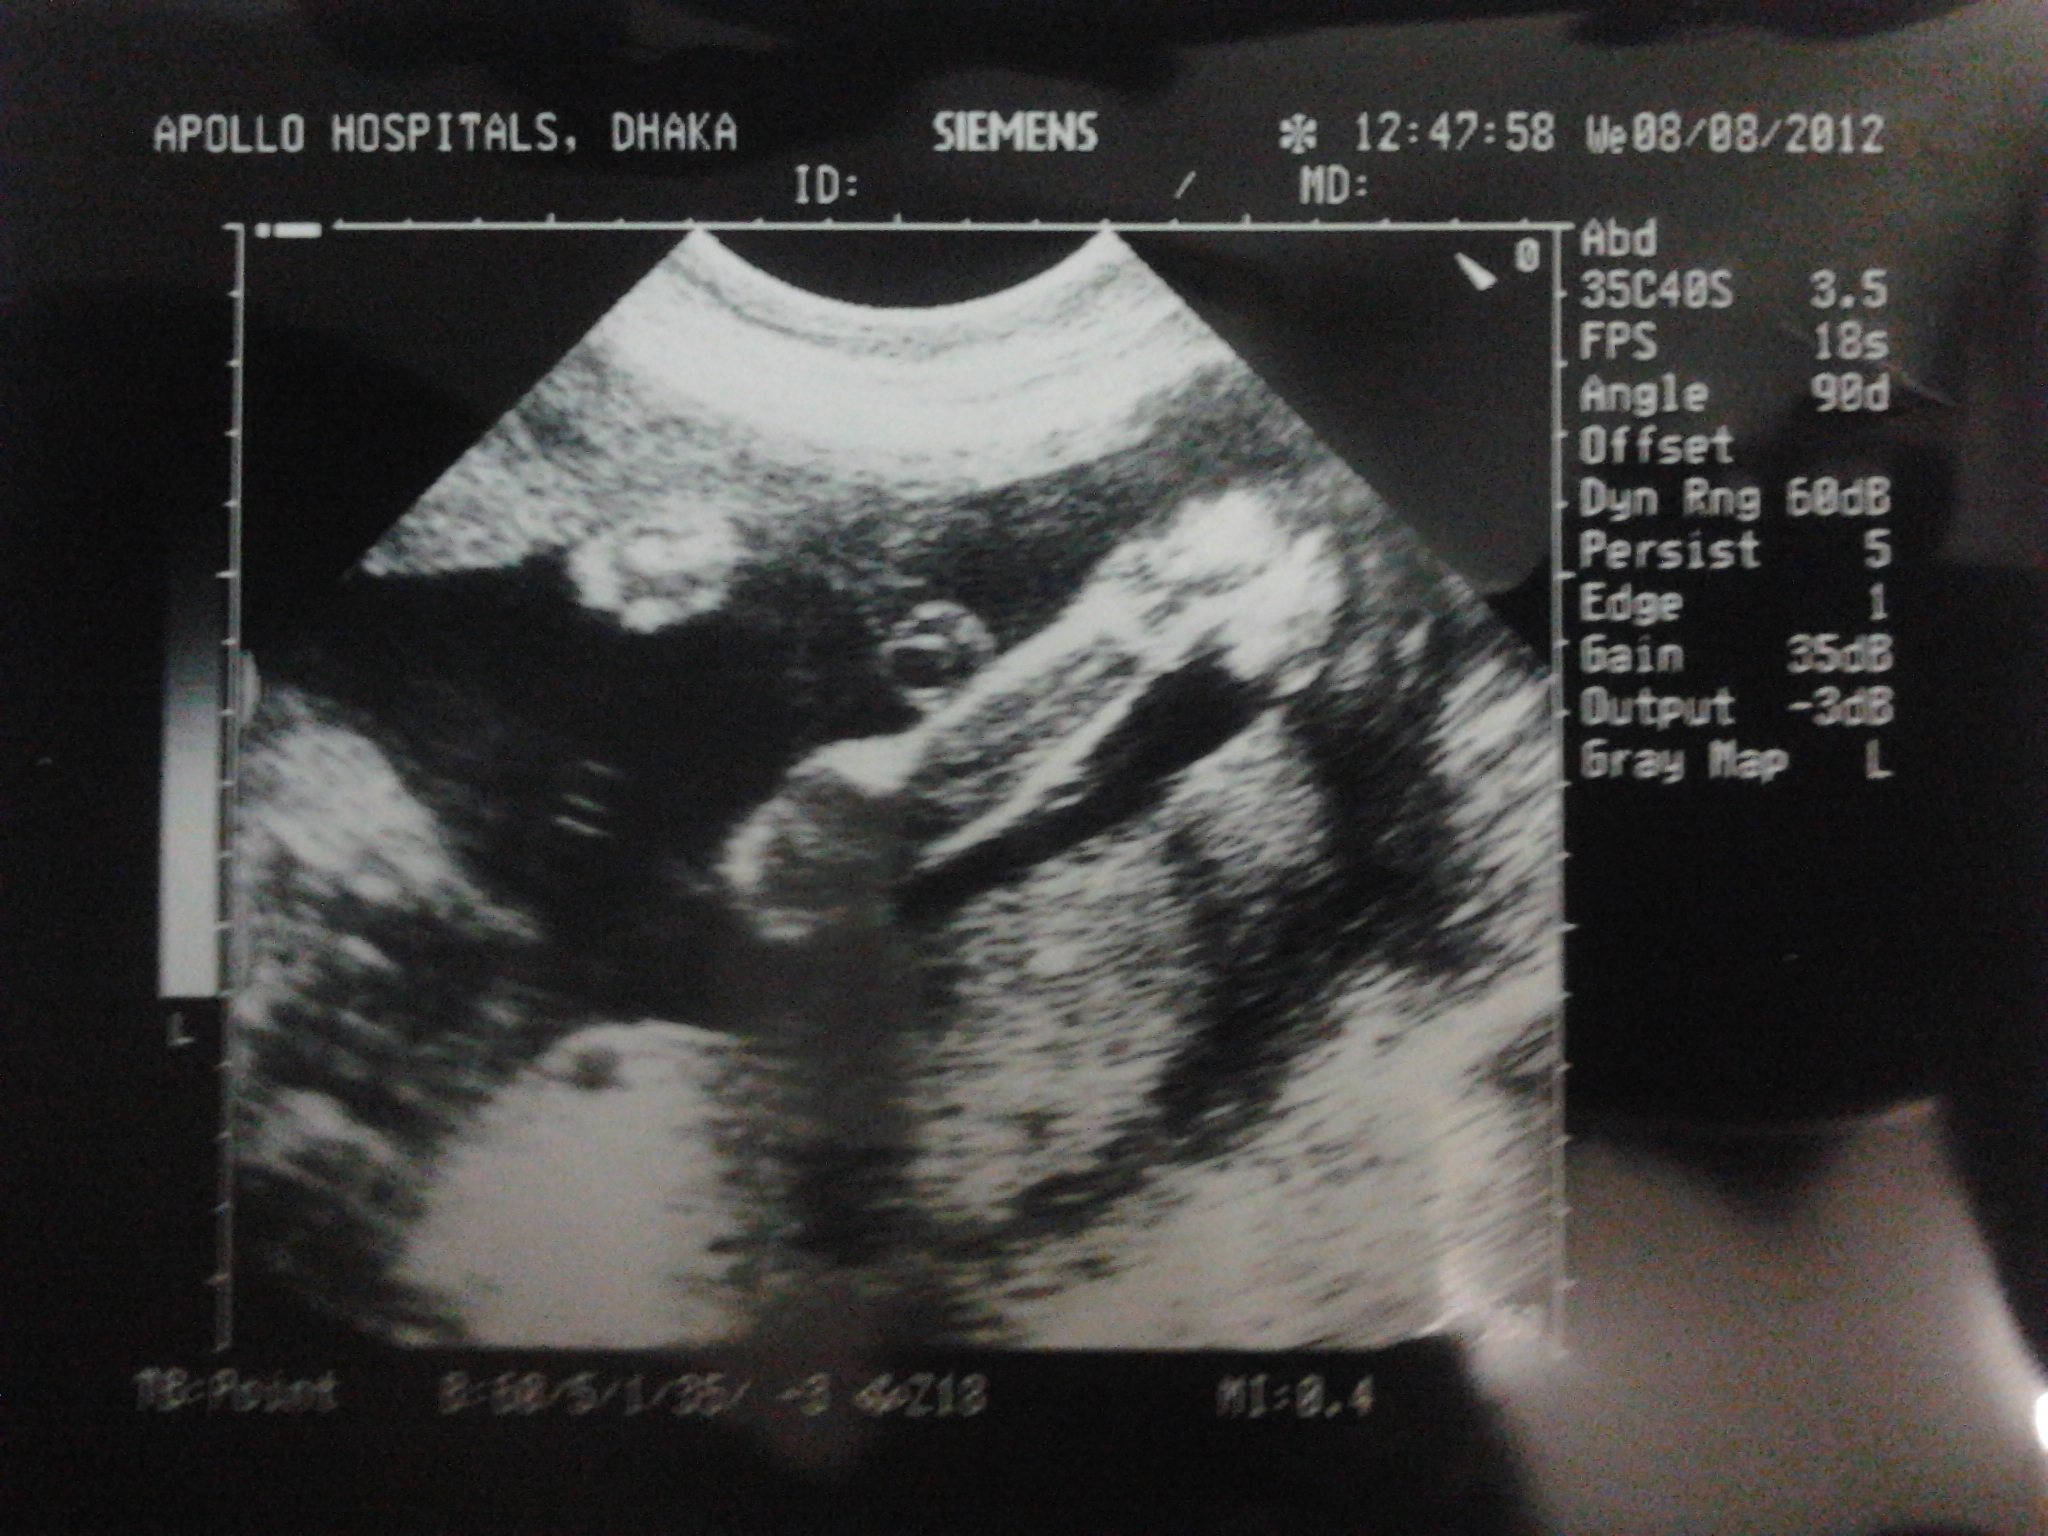

Sorry Razi, I'm not good at all with ultrasounds, I never manage to figure out how baby is positioned let alone seeing his/her genitals or the nub. I always wonder how other girls manage to figure it out! But other girls will be able to help you. Are you swaying pink or blue? good luck with having the baby of your dreams!!